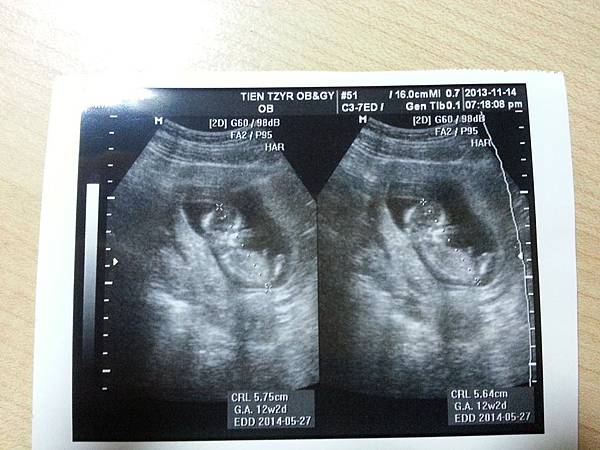

20131115_001346[1].jpg

2013年9月,我們有了這個孩子。

決定懷胎十月,是需要很大的衝動,

拼了命平安的順產,是需要很大的好運。

很幸福的是,土豆太郎在2014.5.19於台大兒童醫院誕生。